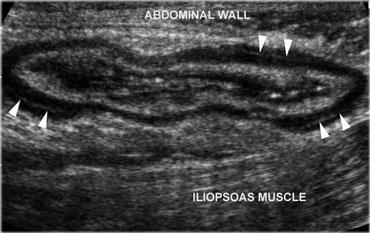

Hồi tràng và ruột thừa bình thường trong khi ép. Thể trạng gầy của bệnh nhân và việc áp dụng kỹ thuật ép cho phép sử dụng đầu dò 13,5 MHz với chất lượng hình ảnh cao.

Khám siêu âm ở bệnh nhân đau bụng cấp đòi hỏi kỹ thuật ép phân độ đặc hiệu.

Bằng cách này, lớp mỡ và các quai ruột được đẩy dạt hoặc bị ép xẹp.

Điều này giúp loại bỏ ảnh hưởng gây nhiễu của hơi trong lòng ruột và rút ngắn khoảng cách từ đầu dò đến ruột thừa, cho phép sử dụng đầu dò tần số cao với chất lượng hình ảnh tốt hơn (Hình).

Kỹ thuật này cũng cho phép đánh giá độ cứng của một cấu trúc thông qua phản ứng của nó khi bị ép. Để tránh gây đau, cần áp lực ép từ từ và nhẹ nhàng, tương tự như thao tác sờ nắn bụng kinh điển.